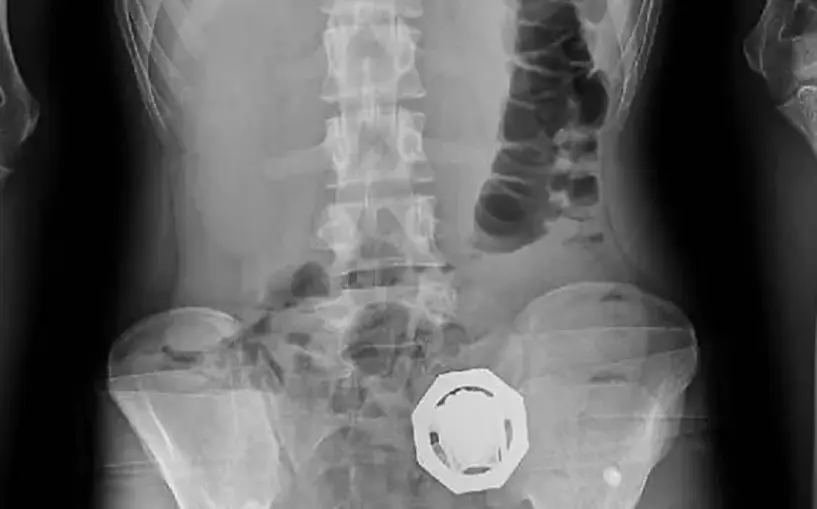

Tedirgin davranışları üzerine adli makamlardan alınan karar doğrultusunda hastaneye götürülen şüphelilerin vücut boşluğu ve bağırsaklarında 121 parça halinde 840 gram eroin bulundu.